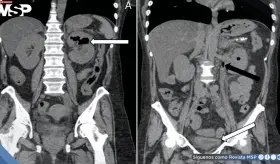

Las imágenes mostraron una aorta abdominal significativamente dilatada, con un diámetro transversal de 4.4 centímetros, muy por encima del límite normal de 3 centímetros.

Paciente presenta ruptura intraperitoneal de quiste parasitario después de presión abdominal súbita, manifestando dolor intenso en hipocondrio derecho con irradiación al hombro.